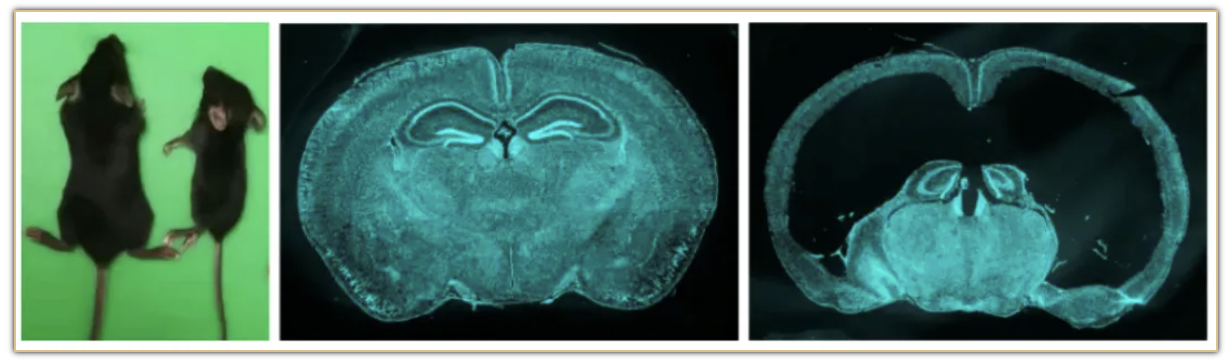

2024年5月13日,戈鹉平实验室联合李灵军和孙文智等团队在Nature Neuroscience上发表了文章The subcommissural organ regulates brain development via secreted peptides(下连合器通过分泌神经肽调节脑发育),该研究系统地揭示了subcommissural organ (SCO, 脑下连合器)作为一个脑内腺体通过分泌神经肽在神经元及大脑生长发育中的起重要角色。研究中构建的Sspo-CreER和Sspo-Cre转基因工具小鼠是SCO研究领域的重要进步,同时,这项工作将为今后研究SCO细胞功能发育提供两个珍贵的遗传操纵工具。

研究者通过将Sspo-Cre和Sspo-CreER与DTA小鼠进行杂交,选择性的去除了子代小鼠的绝大部分SCO细胞。他们发现,当小鼠SCO腺体缺失后,它们体型矮小,行动障碍,总体存活率很差。进一步发现,SCO缺陷小鼠的呈现明显脑积水和脑发育缺陷表型。往脑内注射SCO来源的神经肽可以有效地缓解发育表型。这些结果揭示了SCO是在大脑生长发育中扮演重要角色的腺体(见图)。

在临床工作中存在很多先天性脑发育畸形伴随脑积水症状的患者,有些患儿在出生后甚至胚胎发育期就存在脑部发育异常,但病因不明。SCO相关的神经肽可能作为药物为这些先天性脑积水或者脑发育异常的患者提供潜在的治疗机会。